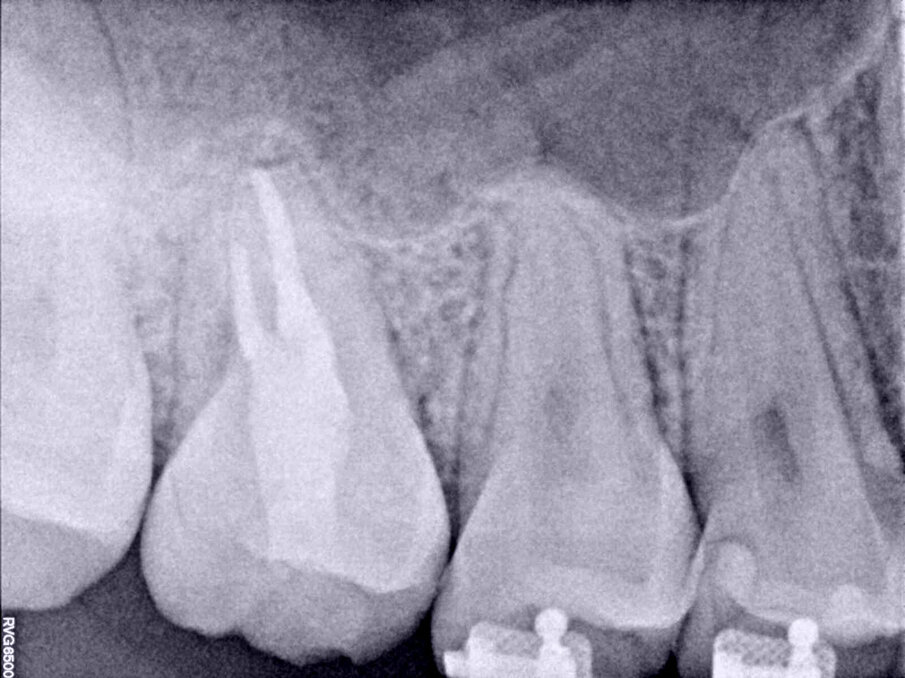

The patient showed up to the clinic eight months later with signs and symptoms of pulp necrosis and acute periapical abscess; a periapical radiolucency was present, and the retromolar area was healed (Fig. 6). In cases like this, where the coronal structure remains intact, it is advisable to take a conservative approach to the root canal therapy, using new technology available in endodontics to achieve good results. The endodontic access opening was created using high-speed burs and ultrasonic tips. The cleaning and shaping protocol was performed with flexible needles and controlled memory files (Aurum Blue, Meta Biomed), especially important properties for entry to the root canals through the conservative access (Figs. 7a & b).

Eight-month post-op radiograph. The retromolar area had healed, but the transplanted tooth showed signs of pulp necrosis and periapical disease.

The use of endodontic files in the stabilised martensitic stage (controlled memory) will offer more resistance against cyclic fatigue.11, 13, 14 A calcium silicate-based endodontic sealer was sonically activated (CeraSeal and EQ-S, Meta Biomed) and gutta-percha was used to obturate the root canals (Figs. 8a–c). This stage of the treatment might be challenging when such a small endodontic access is created. The use of a calcium silicate-based endodontic sealer facilitates the obturation process, and the sonic activation helps to distribute the material all along the cleaned and shaped root canal system (Fig. 9). An adhesive coronal restoration was placed in the same appointment, a dual-polymerised core material (NexCore, Meta Biomed) for the pulp chamber and a compactable composite for the occlusal surface (Ezfil, Meta Biomed; Figs. 10a & b). The patient thereafter began orthodontic treatment, and the tooth was functional and the patient asymptomatic. The three-year follow-up radiograph showed healthy periapical tissue (Fig. 11).